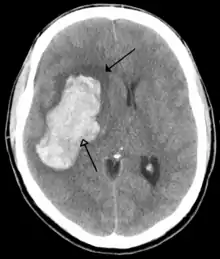

فحص طبي

تم تشخيص السكتة الدماغية من خلال عدة أساليب: فحص للجهاز العصبي (مثل NIHSS)، الأشعة المقطعية في (معظم الأحيان دون تحسينات التباين) التصوير بالرنين المغناطيسي، موجات دوبلر فوق الصوتية، والشرايين. تشخيص السريري للسكتة الدماغية، بمساعدة من تقنيات التصوير. تعمل تقنيات التصوير في تحديد الأنواع الفرعية وسبب السكتة الدماغية. لا يوجد هناك حتى الآن أي اختبار دم يستخدم عادة لتشخيص السكتة الدماغية نفسها، على الرغم من اختبارات الدم قد تكون عوناً في معرفة السبب المحتمل من السكتة الدماغية.[54]

التصوير

في الجلطة الدماغيه الاسكيمية [55]

- الأشعة المقطعيه

حساسية = 16٪ خصوصية = 96٪

- التصوير بالرنين المغناطيسي

حساسية = 83٪ خصوصية = 98٪

الجلطة الدماغية النزيفية

- الأشعة المقطعية (بدون تحسينات على النقيض)

حساسية = 89٪ خصوصية = 100

حساسية = 81٪ خصوصية = 100 للكشف عن نزيف مزمن، أشعة الرنين المغناطيسي هو أكثر حساسية. فبالتالي هو أفضل .[56]